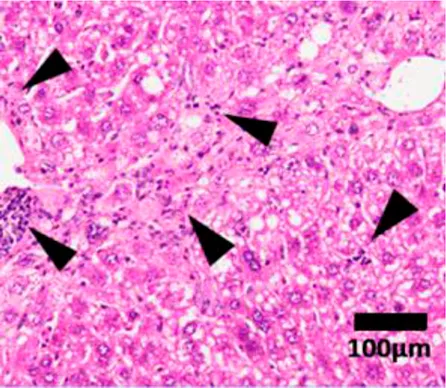

Steatosis![]() | 0 | <5% of liver tissue (per field of view) |

| 1 | <33% of liver tissue (per field of view) | |

| 2 | 34–66% of liver tissue (per field of view) | |

| 3 | >66% of liver tissue (per field of view) | |

NAFLD Activity Score (NAS) system with representative H&E images. The NAS system is an internationally recognized method of determining the severity of fatty liver disease (see text for references). Steatosis score represents the percentage of lipid droplets present in each field of view, inflammation score represents the number of inflammatory cell clusters (1 cluster = 1 foci) and the ballooning score is indicative of the number of hepatocytes that have altered cell structure due to excess lipid accumulation. The pathologist can give a score between 0 and 3 for each of steatosis and inflammation, and 0–2 for ballooning, based on the characteristics of the samples. Combining the scores from each of the parameters give rise to the total NAS. H&E-stained representative images are provided by our laboratory. All images were taken under ×200 magnification. Black arrows are marking the specific location of the histological features.